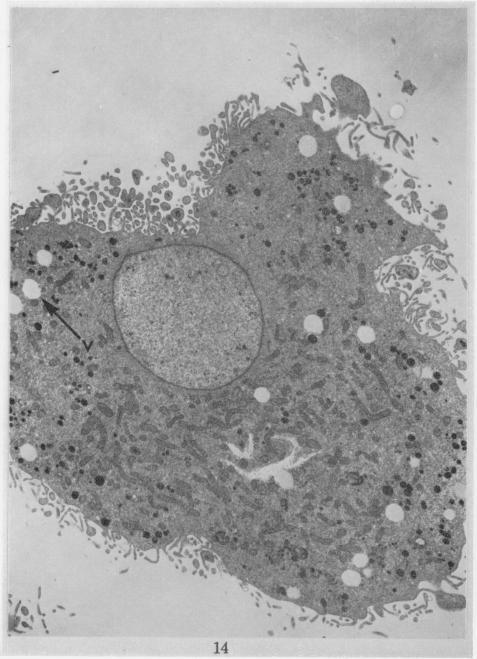

The pleomorphic cytology of the HT-1 cell line is described. Cytochemical studies indicated the presence of glycogen and lysosomes in these cells. Cytogenetic studies demonstrated the presence of a large telocentric chromosome (M1) and two minute chromosomes (M2) not found in normal hamster cells. A cloned line was isolated which did not contain these marker chromosomes. All cells were hyperdiploid with chromosome number around triploidy, although none was a true triploid. Ultrastructural studies revealed the presence of "nuclear bodies", "dense bodies" and "interchromatinic granules" which have been previously described in viral induced malignancies. A few of the cells contained in their cytoplasm structures of approximately 700 [unk] in diameter which bore some resemblance to immature virus particles. Both light and electron microscopy demonstrated some nuclei lacking chromatin aggregates. This is interpreted to mean that the total genetic material of these nuclei was dispersed as free DNA not linked with histone to form chromatin aggregates.

描述了HT - 1细胞系的多形性细胞学特征。细胞化学研究表明这些细胞中存在糖原和溶酶体。细胞遗传学研究证明存在一条正常仓鼠细胞中未发现的大型端着丝粒染色体(M1)和两条微小染色体(M2)。分离出了一个不含有这些标记染色体的克隆系。所有细胞均为超二倍体,染色体数约为三倍体,但没有一个是真正的三倍体。超微结构研究揭示了“核体”、“致密体”和“染色质间颗粒”的存在,这些在病毒诱导的恶性肿瘤中已有描述。一些细胞的细胞质中含有直径约700 [未知单位] 的结构,与未成熟病毒颗粒有一些相似之处。光学显微镜和电子显微镜均显示一些细胞核缺乏染色质聚集体。这被解释为意味着这些细胞核的全部遗传物质以游离DNA的形式分散,未与组蛋白连接形成染色质聚集体。